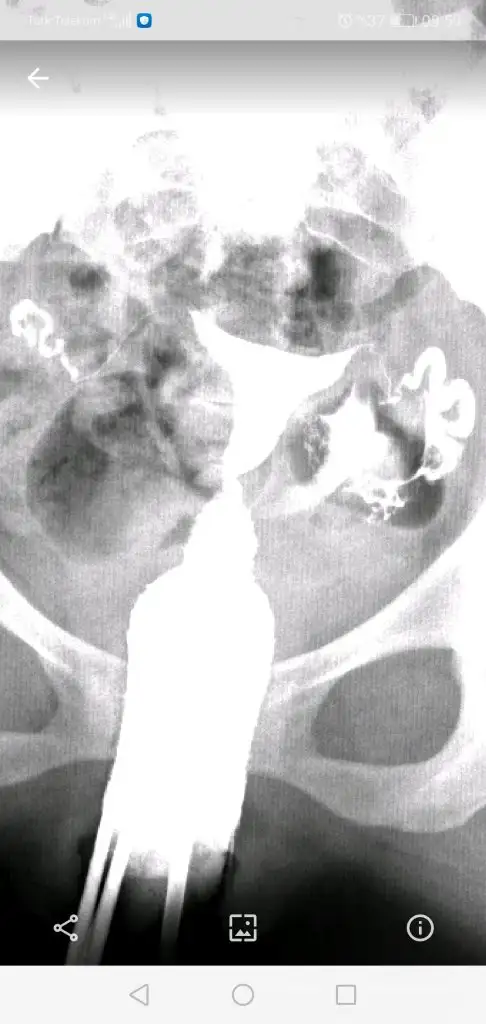

Tüh olsaydı bakardın. Bak benimki böyleDemek o yüzden sisteme düşmüyor, cd var ama açacak bilgisayar yoko gün doktorun dediği ve kağıtta yazan rapor var işte görüntüyü merak ettim

Çok Merak ettim şimdiTüh olsaydı bakardın. Bak benimki böyle